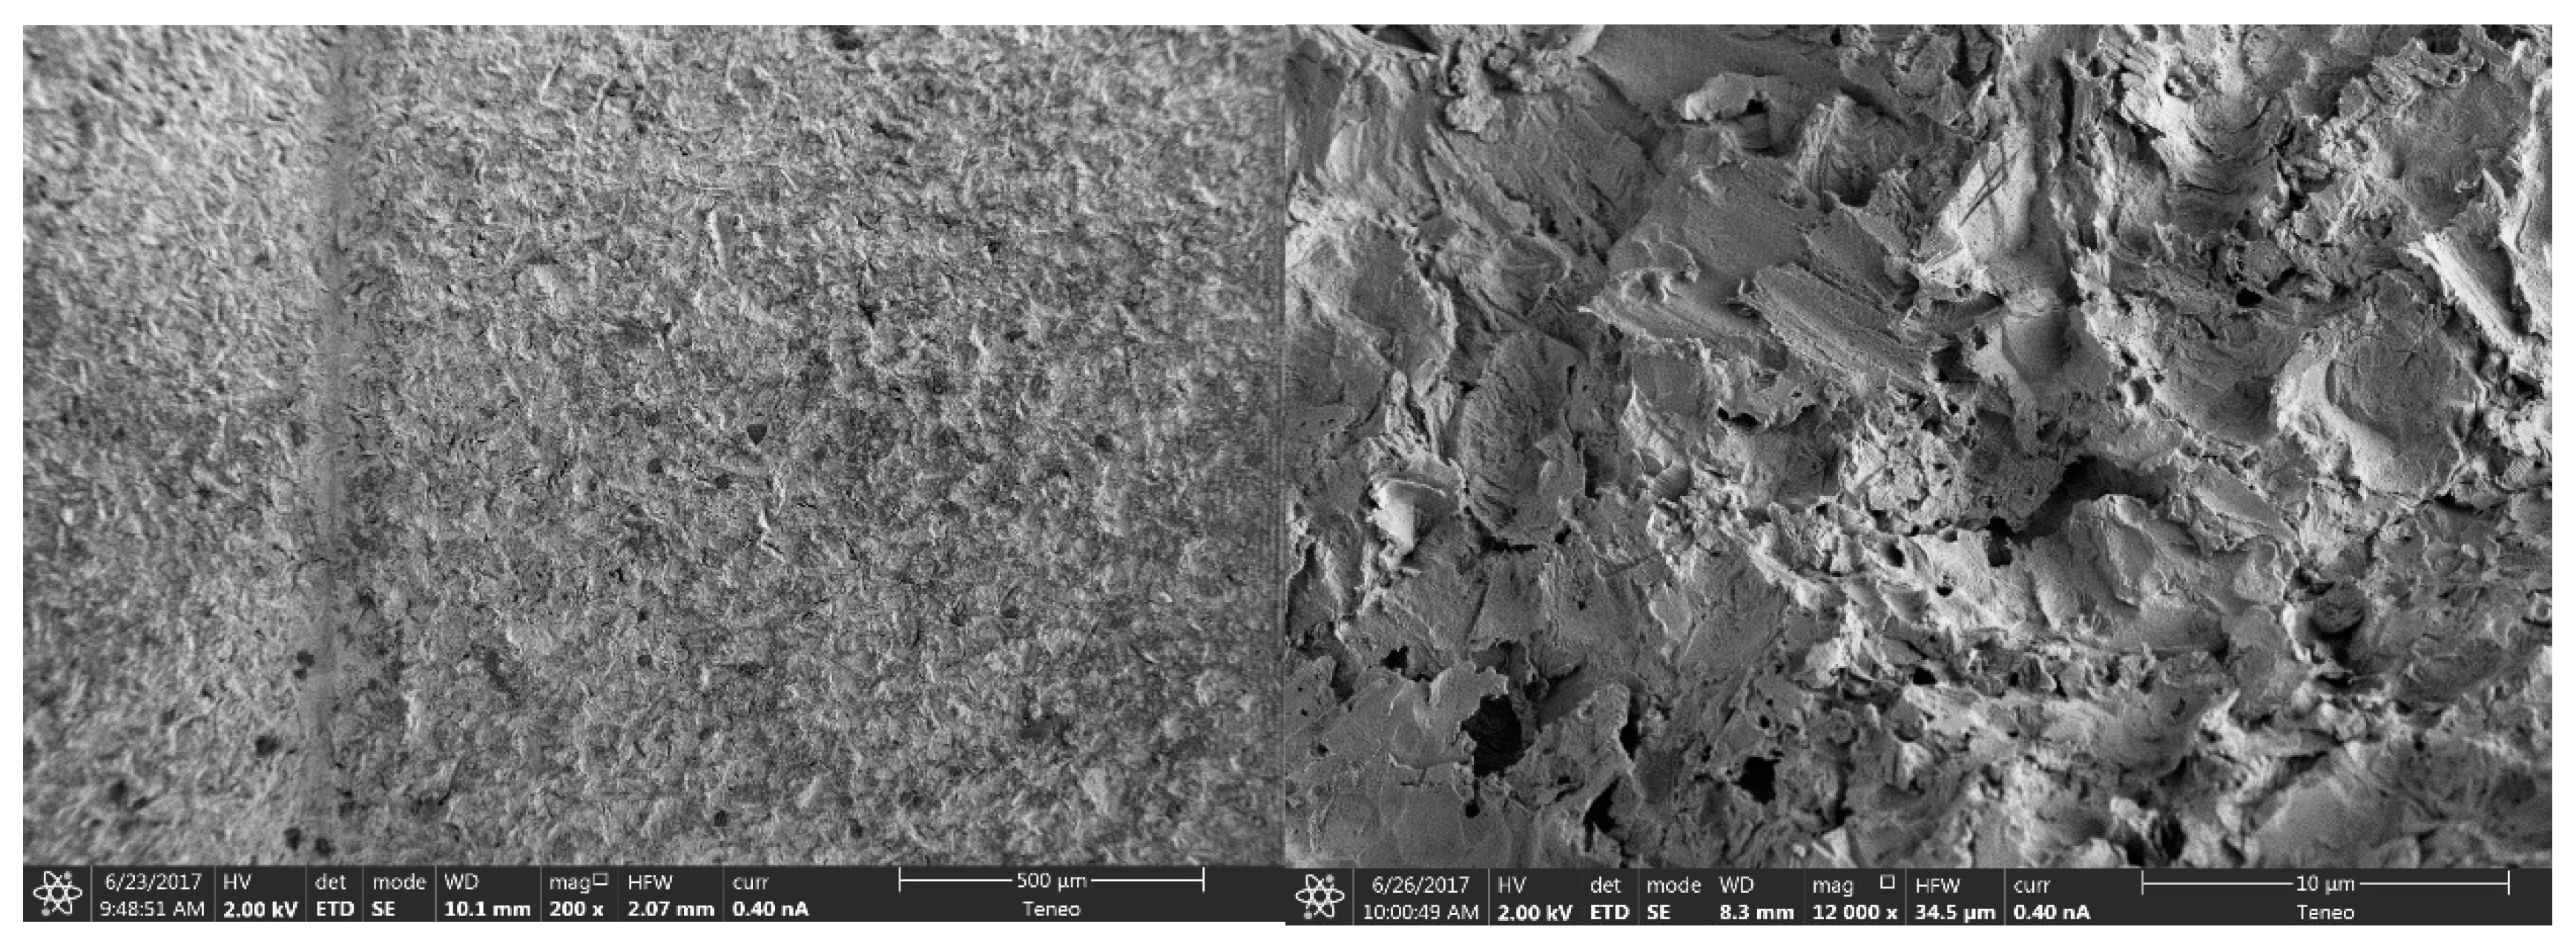

2.2.1. Morphological Analysis of the Surface

3.1.1. Morphological Analysis of the Surface